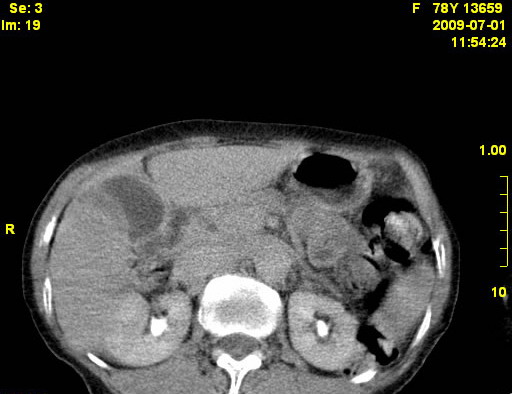

以下是引用zjzjr在2009-7-3 11:02:00的发言:[br]动脉期不均匀强化,门脉期及延迟期强化明显,肝门部见肿大淋巴结影,肝内胆管扩张.考虑肝右叶前段胆管细胞癌伴肝门淋巴结转移,胆内胆管扩张.慢性胆囊炎.

以下是引用dsl555在2009-7-4 10:59:00的发言:[br]考虑肝右叶前段胆管细胞癌伴肝门淋巴结转移,胆内胆管扩张.慢性胆囊炎. [br][br]支持。